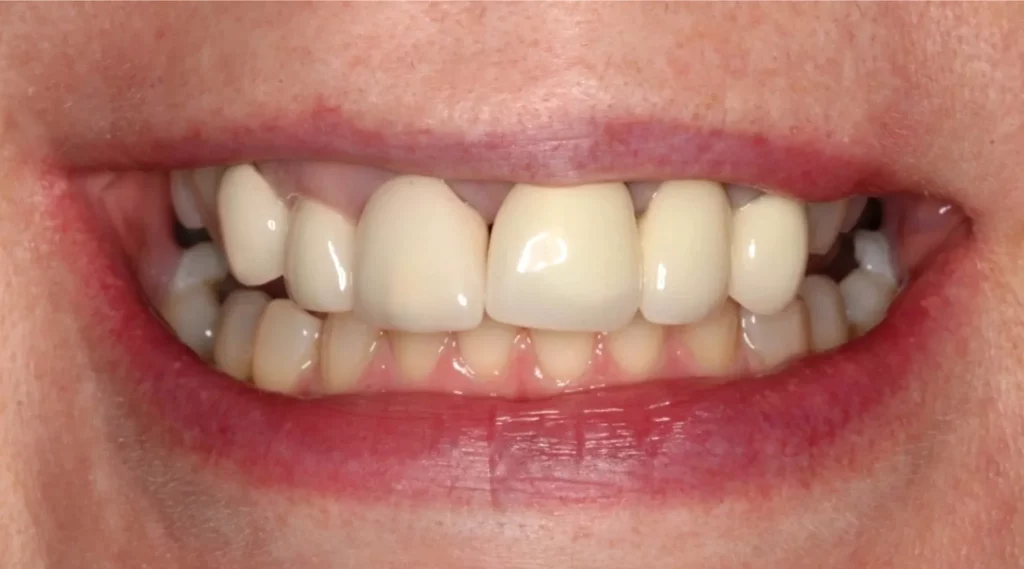

This lady attended Gentle after a previous implant had not worked. In the left photo below is a temporary bridge that kept falling out, which was frustrating for the patient, so she wanted to try again with implant treatment. Moreover, when she smiled, the adjacent eye tooth had an exposed root, so it looked too long. At the same time as placing gum around the implant, a gum graft was placed to cover the exposed eye tooth root. This improves the overall aesthetic outcome for the patient. Below on the right you can see how we took time to rebuild the bone and gum in the first phase of treatment, which gave the implant a solid foundation to sit in.

The implant was placed into the bone, under the gum, and a white post was chosen to fit into the implant to maximise the final crown’s appearance. The after photo was taken 5 years after the implant was placed and shows how nicely the work is performing.